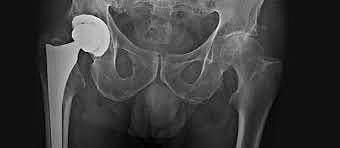

Austin T. Moore (1899-1963) publicó y realizó la primera sustitución metálica de la cadera

Ronald Lawrie Huckstep (1926) Inventó el primer clavo acerrojado en 1967 y la primera prótesis de cadera no cementada en 1979. Fue un pionero en el uso de la aleación de titanio para implantes en 1972. Se convirtió en catedrático de Traumatología y Cirugía Ortopédica en la Universidad de Gales del Sur en 1972 y ha publicado cinco libros sobre fiebre tifoidea, poliomielitis, trauma y Ortopedia.